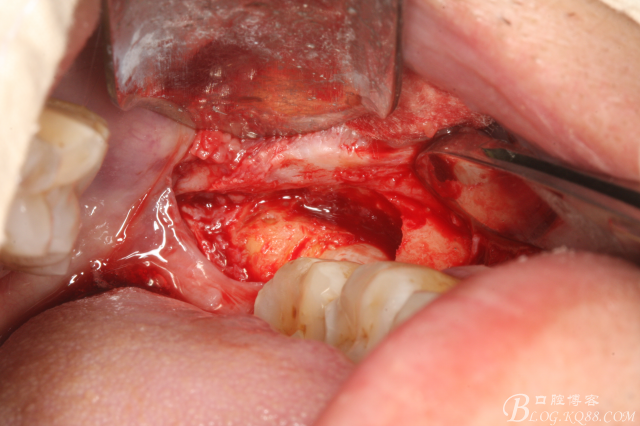

二、手術(shù)過程

圖2.切開、翻瓣、去骨

圖三、完全暴露38牙根和牙冠